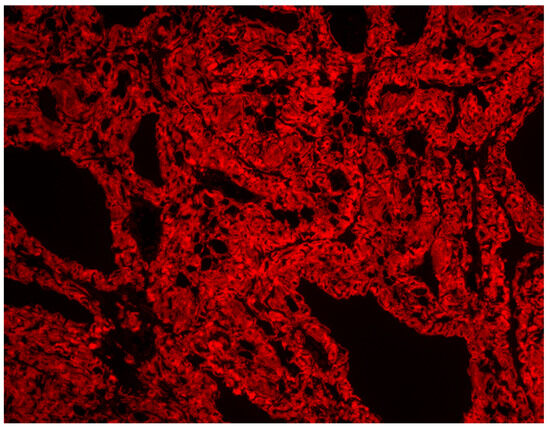

A Rare Case of Systemic Amyloidosis Involving the Thyroid in a Young Patient

by Oliwia Julia Kasprzak, Kamila Stępińska, Kaja Kiedrowska, Tomasz Błaszkowski, Aleksandra Kudrymska, Sylwia Sikora, Maciej Miernik and Maciej Romanowski

J. Clin. Med. 2025, 14(19), 6741; https://doi.org/10.3390/jcm14196741 - 24 Sep 2025

Thyroid amyloidosis is a rare condition associated with thyroid pathologies such as medullary carcinoma, papillary carcinoma, amyloid goitre, and benign lesions, with a clinically palpable goitre being exceptionally uncommon. As a result, many cases of benign thyroid enlargement caused by amyloid deposits remain [...] Read more.

Thyroid amyloidosis is a rare condition associated with thyroid pathologies such as medullary carcinoma, papillary carcinoma, amyloid goitre, and benign lesions, with a clinically palpable goitre being exceptionally uncommon. As a result, many cases of benign thyroid enlargement caused by amyloid deposits remain undiagnosed. A 28-year-old male patient noticed progressive neck circumference enlargement, voice alteration, decreased appetite, weight loss, dysphagia, fever, and night sweats. Fine-needle aspiration biopsy of the thyroid gland did not reveal the cause of the goitre. A total thyroidectomy was performed. Histopathological examination confirmed advanced thyroid amyloidosis. Full article

Show Figures

Figure 1